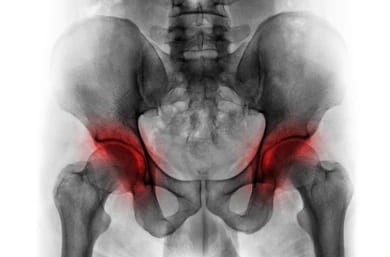

골반괴사는 골반 주위의 뼈가 혈액 공급을 충분히 받지 못해 괴사 하는 질병입니다. 이로 인해 뼈가 약화되고 통증이 동반됩니다. 이때 음식은 어떻게 골반괴사 예방과 치료에 도움이 될까요? 뼈 건강을 유지하는 데 필수적인 영양소를 음식으로 섭취함으로써 골반괴사를 예방하거나 증상을 완화할 수 있습니다. 칼슘, 비타민 D, 마그네슘 등 뼈 건강에 좋은 영양소를 충분히 섭취하는 것이 중요합니다. 이러한 영양소는 음식으로 쉽게 얻을 수 있어서 약에 의존하지 않고도 건강을 관리 수 있습니다.